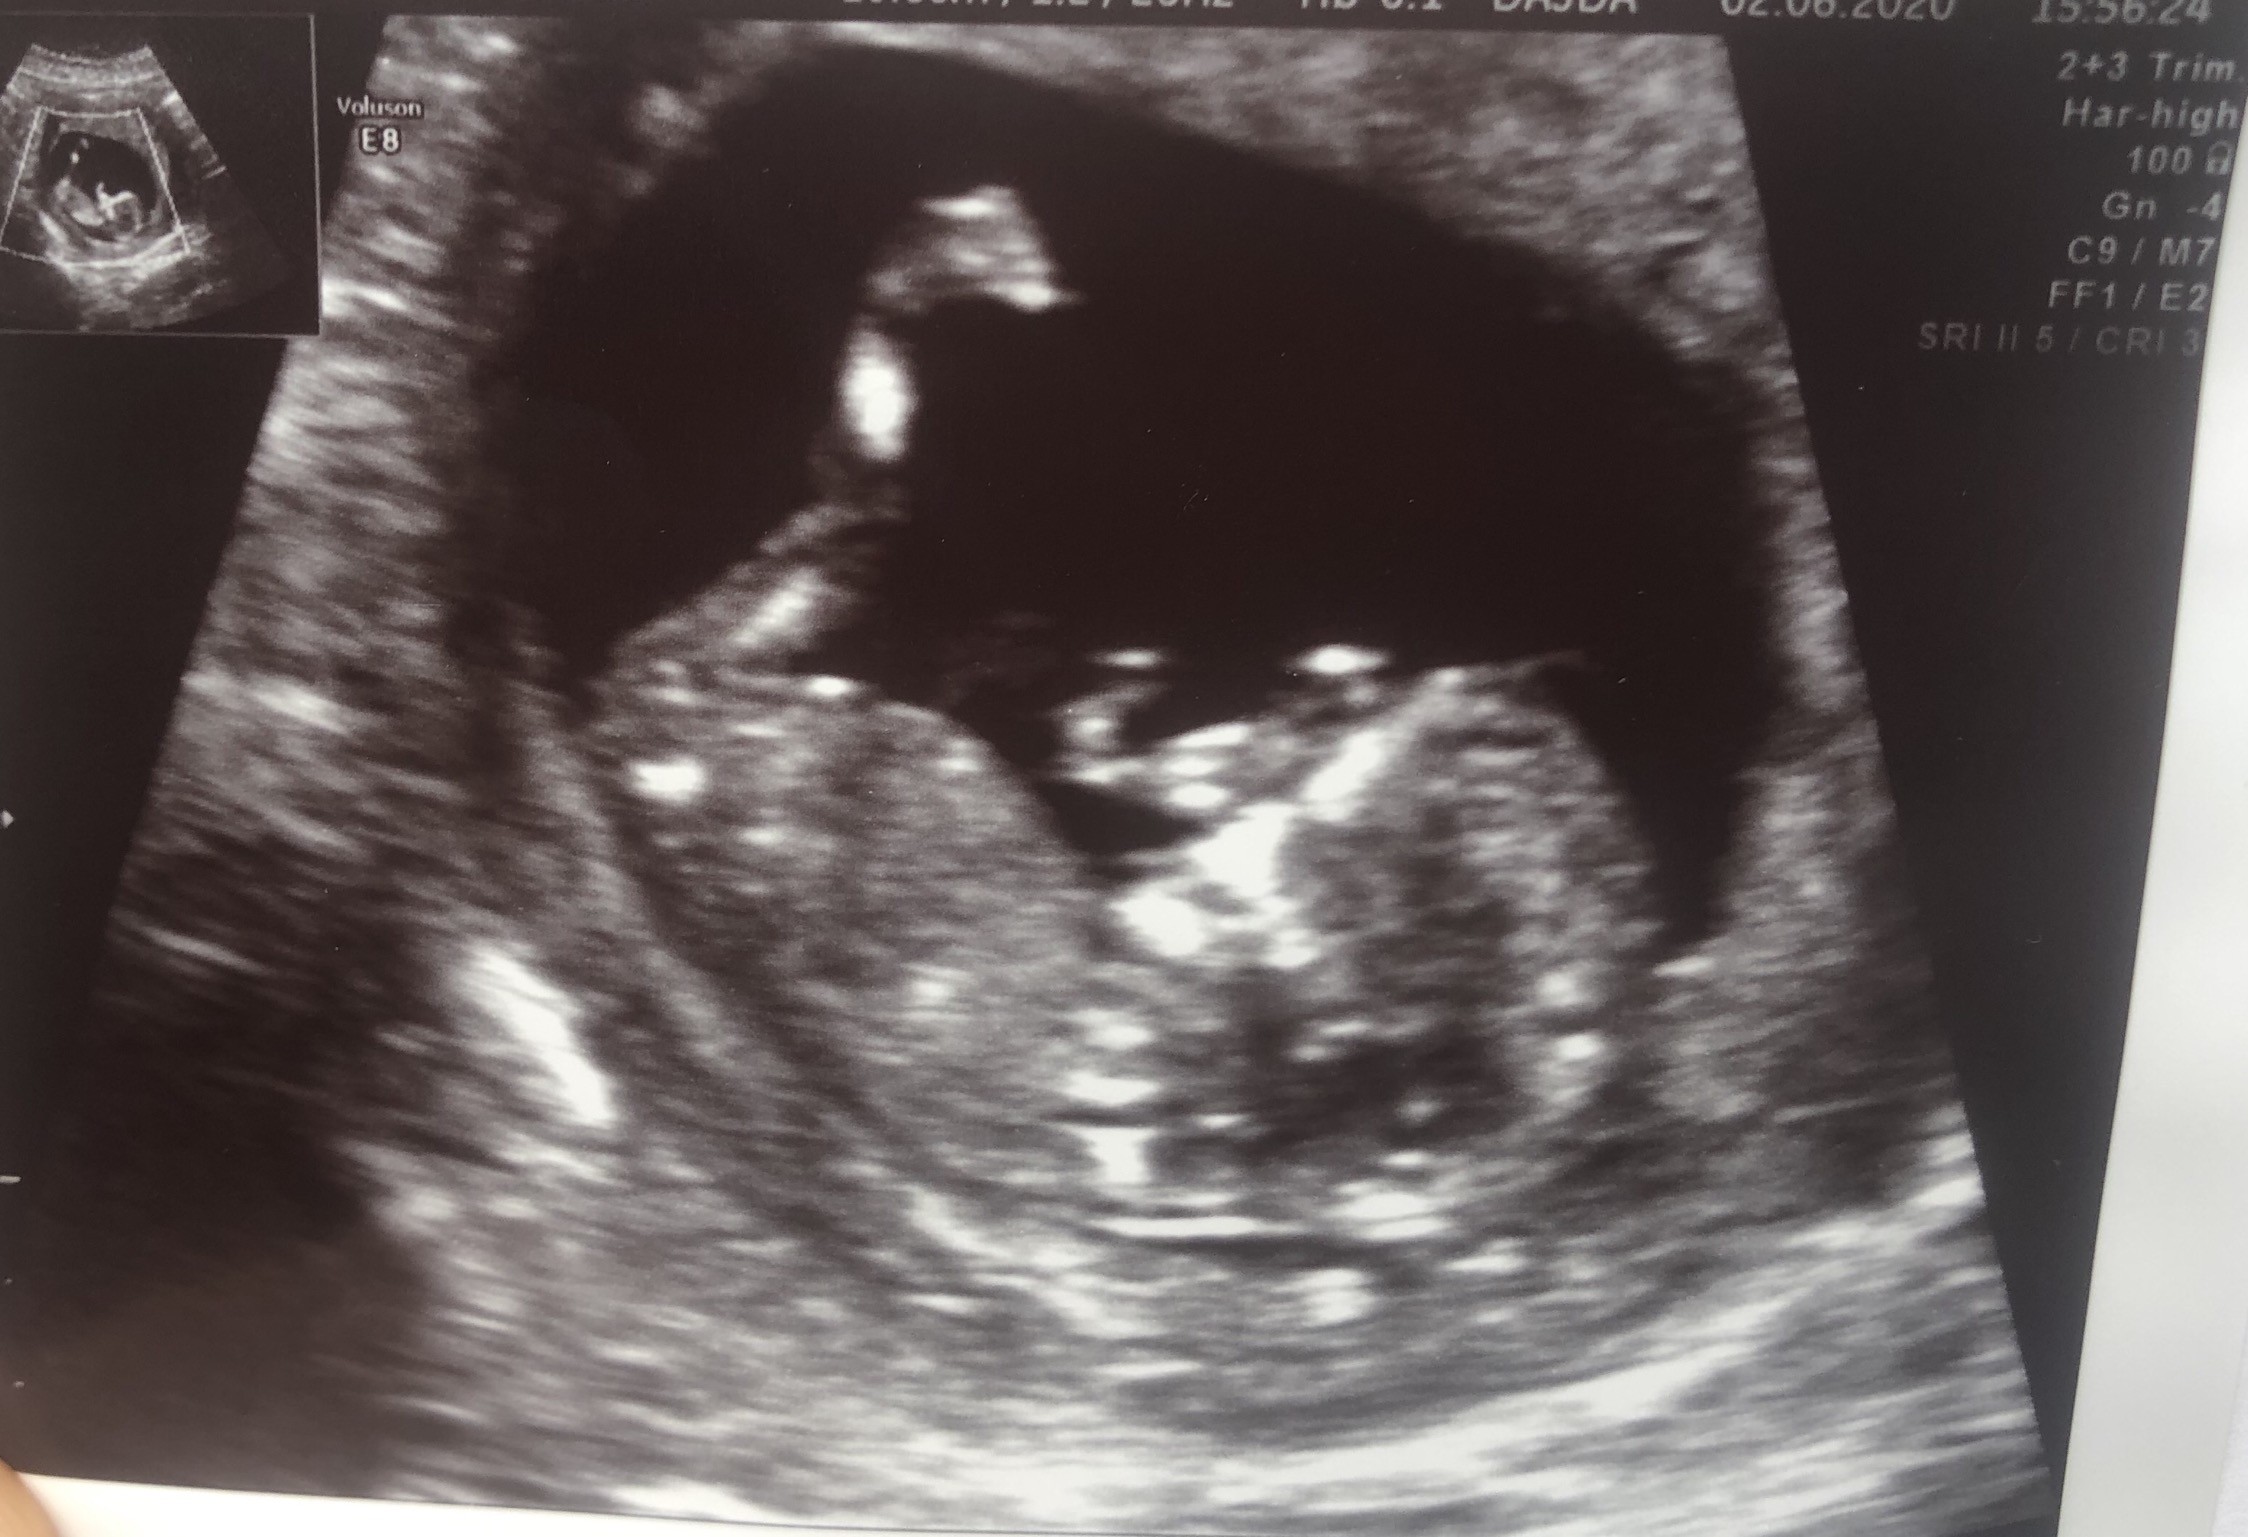

Czesc dziewczyny.. nie odzywam sie prawie wgl bo nie mam czasami sily. Do pracy ledwo wstaje pozniej cos ogarniam potem drzemka kolacja kapiel i tak w kolko :/ jestem bardziej zmeczona niz w pierwszych tygodniach. Poinformowalam przelozona o ciazy bo juz czasami nie mialam sily sie wykazac w pracy i o dziwo przyjela to spokojnie i pogratulowala oczywiscie. Kamien z serca mi spadl jak powiedzialam. Na zamknieta grupe nie zasluguje ale kazdy post czytam i chcialam wszystkim Wam pogratulowac zdrowych dzieciaczkow. Te wasze zdjecia sa przeslodkie ☺️🙈 sama nie moge sie doczekac prenatalnych a mam w srode. Mam nadzieje ze dzidzia bedzie zdrowa.. Ostatnio jak bylam z wynikami badan u mojej gin to dzidzia wykopywala tak nozka ze pani doktor zdazyla to uchwycic.

• EB254498-0C6D-4AC4-A294-D5B4738F1F74.jpeg

EB254498-0C6D-4AC4-A294-D5B4738F1F74.jpeg

464,8 KB · Wyświetleń: 112